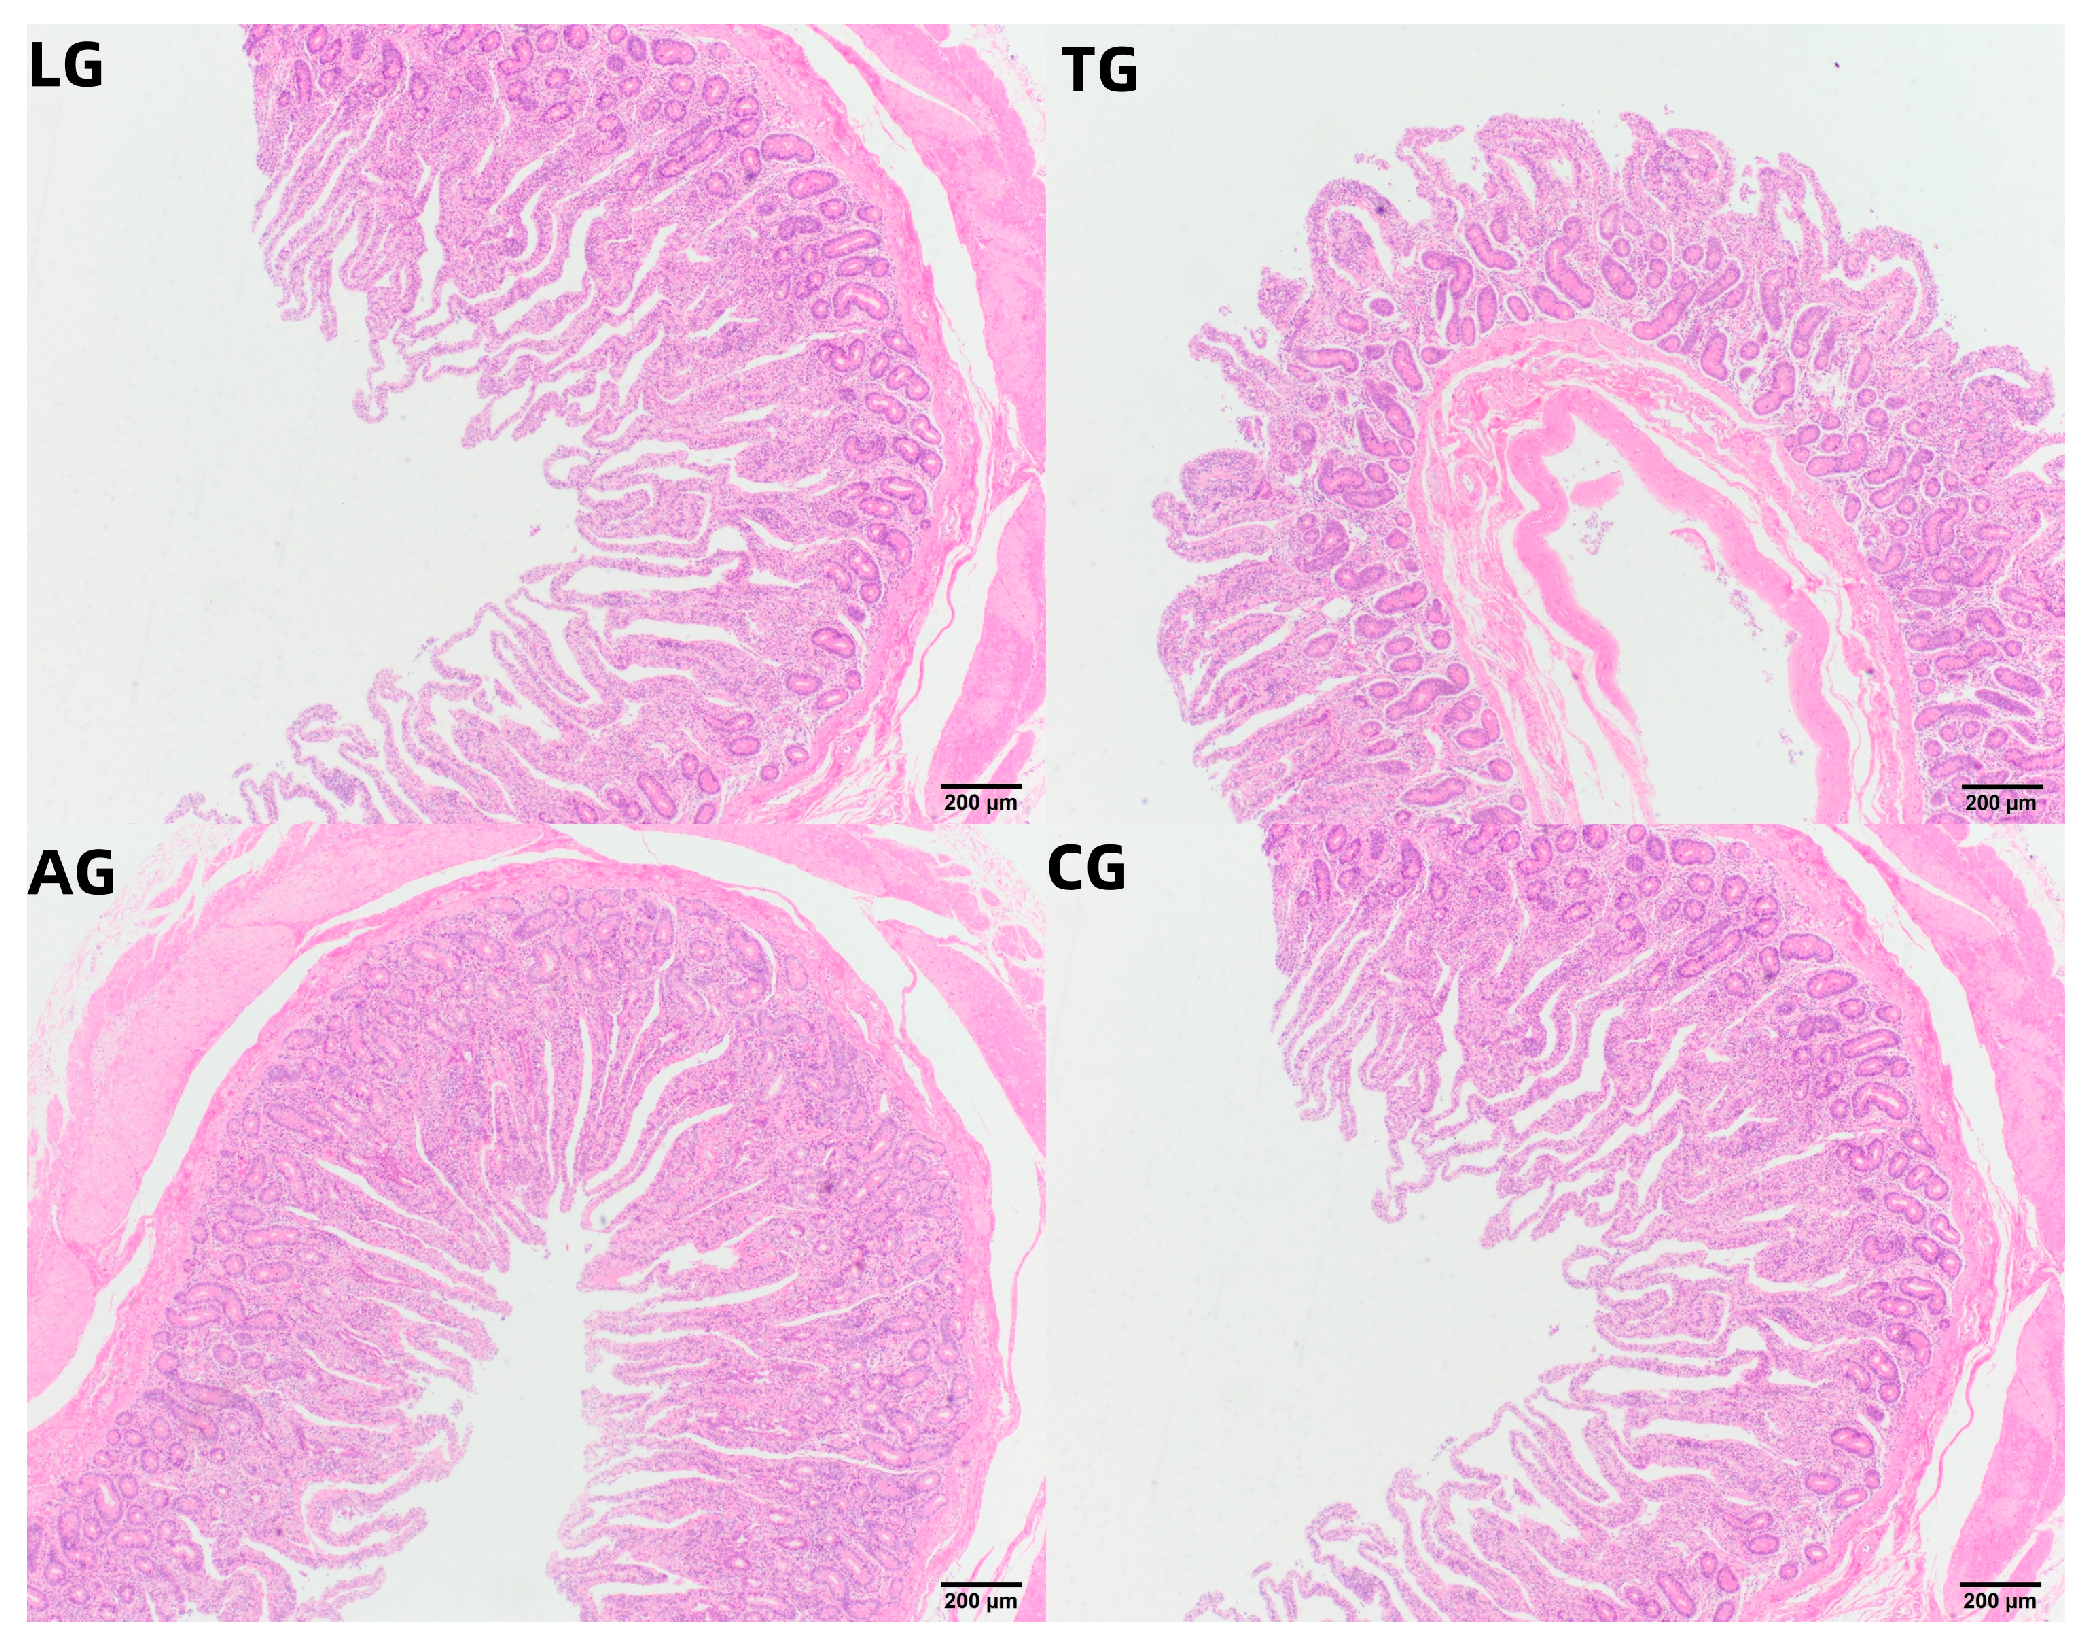

| Treatment | Villus Height (VH) | Crypt Depth (CD) | VH/CD |

|---|---|---|---|

| TG | 321.05 ± 19.05 c | 165.85 ± 9.55 c | 1.94 ± 0.25 b |

| LG | 463.15 ± 13.35 a | 220.50 ± 11.35 a | 2.10 ± 0.12 b |

| AG | 398.25 ± 11.55 b | 165.75 ± 10.50 c | 2.40 ± 0.23 a |

| CG | 409.20 ± 15.60 b | 198.05 ± 12.85 b | 2.07 ± 0.43 b |